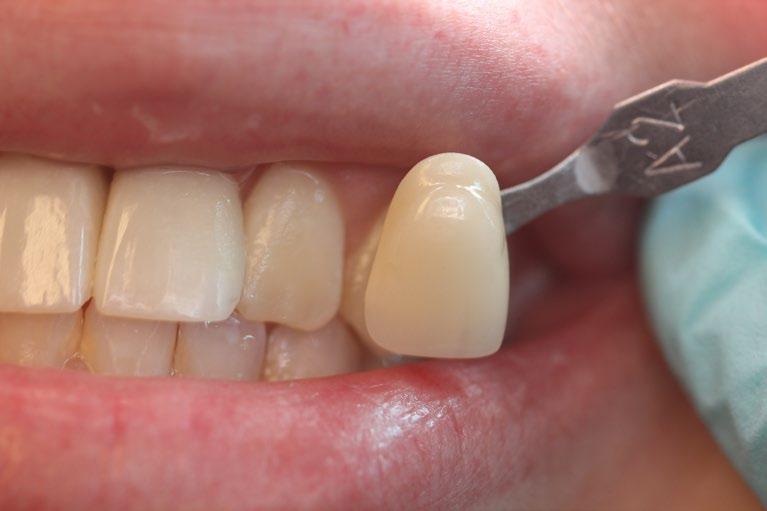

Creating a New Look with Dental Implants

One of the most significant advantages of dental implants is their ability to restore a natural-looking smile. They are customdesigned to match the natural color and shape of the patient’s existing teeth, blending seamlessly into the mouth. This can dramatically improve a person’s appearance, making them look younger and healthier. For many, this can lead to a renewed sense of self-esteem and vitality, particularly important as they age.

The Impact on Confidence